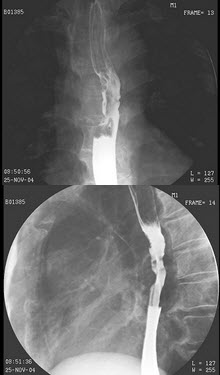

B.B环

B.结核性胸膜炎